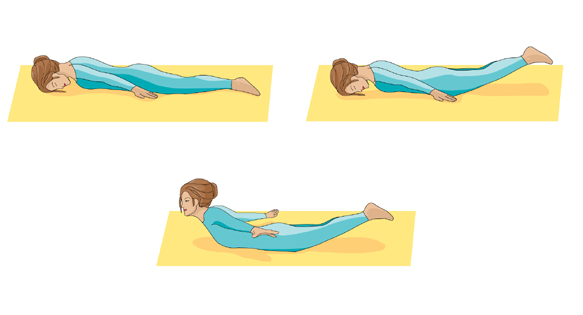

مکانیسم های مختلف شکستگی ستون فقرات گردنی گردنی در شکل های روبرو و زیر آمده است.